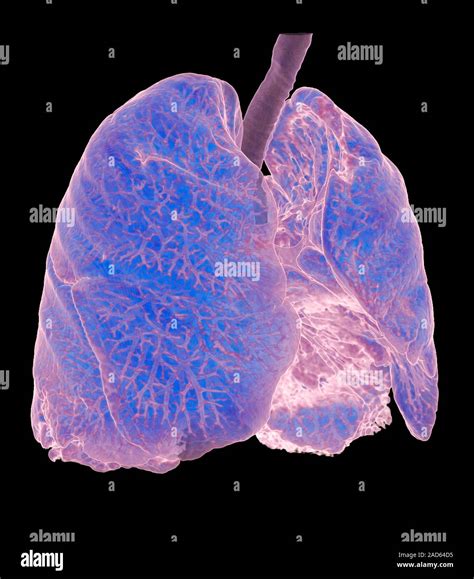

Receiving medical imaging results can often feel overwhelming, especially when terms like lung scarring on CT scan appear on your radiology report. Finding evidence of scarring—medically referred to as pulmonary fibrosis or interstitial lung abnormalities—can trigger anxiety, but it is important to remember that these findings are descriptive and require clinical context to be fully understood. A CT scan is a highly sensitive diagnostic tool that provides a detailed cross-sectional view of the lungs, allowing doctors to identify changes in the lung tissue that might not be visible on a standard chest X-ray. Understanding what this scarring means, why it happens, and what steps you should take next is the first step toward managing your respiratory health effectively.

When a radiologist identifies lung scarring on CT scan, they are typically referring to the presence of fibrotic tissue. In a healthy lung, the tissue is delicate, thin, and elastic, allowing it to expand and contract effortlessly with every breath. When injury occurs, the body attempts to repair the tissue; however, in certain conditions, this repair process goes awry, leading to the buildup of excess connective tissue.

This scarred or thickened tissue is less flexible than healthy lung tissue. Over time, as this scarring accumulates, it can make the lungs stiff, making it more difficult for oxygen to pass from the air sacs (alveoli) into the bloodstream. This physiological change is what leads to symptoms such as shortness of breath and a persistent, dry cough.